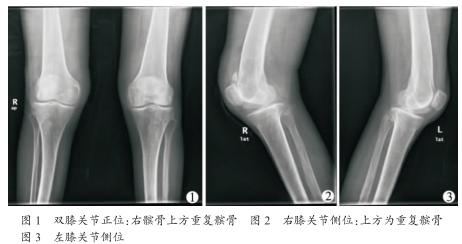

重复髌骨1例